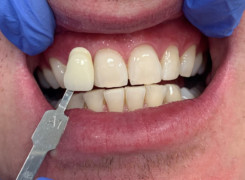

Pan Ryszard trafił do Naszego Gabinetu z jasno sprecyzowanym oczekiwaniem. Miał 84 lata i chciał odzyskać możliwość swobodnego spożywania posiłków oraz poprawienia sobie komfortu życia a także prosił aby przywrócić mu piękny uśmiech jakim cieszył się przed laty. Już na początku pierwszej rozmowy zastrzegł, że interesuje go wyłączenie rozwiązanie uzupełnieniem protetycznym stałym. Nie miał zamiaru użytkować żadnych protez ruchomych. Mając na uwadze powyższe wykonaliśmy Panu Ryszardowi zdjęcie pantomograficzne oraz badanie tomograficzne szczęki i żuchwy na postawie których zapanowywaliśmy Pacjentowi optymalne rozwiązanie – stałe uzupełnienie protetyczne w postaci 28 koron cyrkonowych zamontowanych do dwóch belek cyrkonowych które będą przymocowane do 16 implantów w konfiguracji 8 wszczepów w szczęcie 8 w żuchwie. Po omówieniu powyższego planu przystąpiliśmy do Wspólnej pracy której efekty w poszczególnych etapach prezentujemy poniżej.